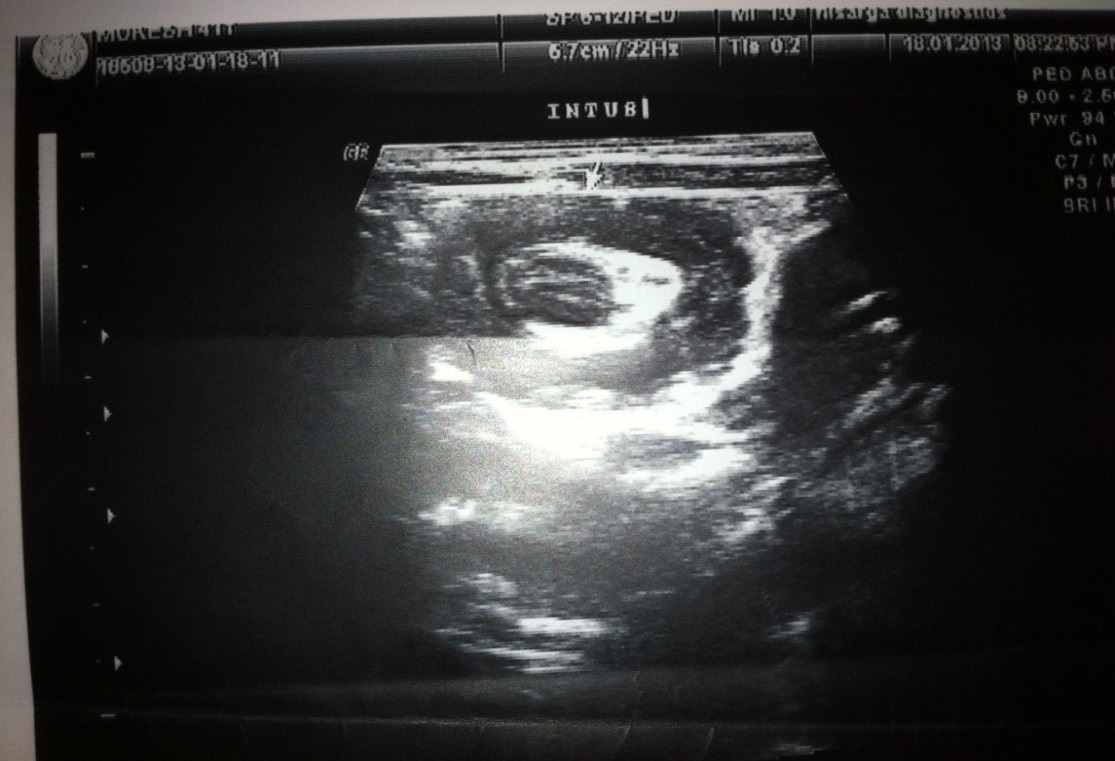

Ultrasonography:

• All patients underwent USG

• Doppler was used to determine bowel ischemia; guides reduction decisions

• Ultrasonography was diagnostic in 93% of our cases

Abdominal ultrasound:

Replaced abdominal radiograph as primary screening modality

• Sensitivity 98 -100%; specificity 88 -100%

• Appearance: outer hypoechoic region surrounding an echogenic center or multiple concentric rings

• Use Doppler to determine bowel ischemia; guides reduction decisions

• Guide hydrostatic and pneumatic reduction